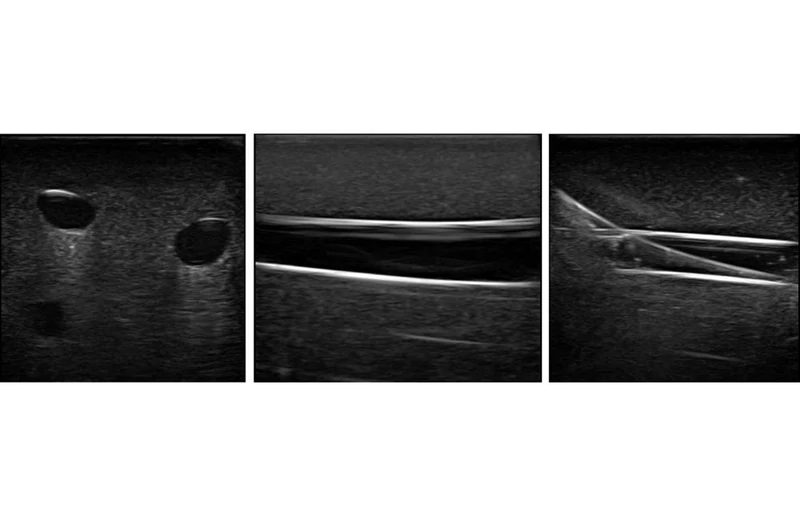

Using Blue Phantom proprietary simulated human tissue, this very realistic and ultra-durable venous access medical model is excellent for training clinicians in the psychomotor skills associated with ultrasound guided venous and arterial access procedures. These ultrasound imaging skills include; using ultrasound system controls, transducer positioning and movement, recognition of arterial and venous anatomy, using ultrasound to target the appropriate vessels for cannulation, and using ultrasound to guide venous access and arterial access procedures in the arm.

Each model offers the vascular anatomy of the entire arm including the brachial artery, brachial and basilic veins, radial artery, ulnar artery, medial cubital vein and the cephalic vein. Excellent for new users as well as more experienced users who are refining their vascular access procedural skills, the vessels in this ultrasound guided venous access and arterial access medical training mannequin can be accessed with needles as well as fluid can be injected into the model to verify needle tip location. Positive fluid flow in the vessels provides users with immediate feedback when vessels are accessed. Arterial pulse can be palpated and visualized under ultrasound with included hand bulb. The chest piece vascular anatomy contains the superior vena cava and subclavian vein.